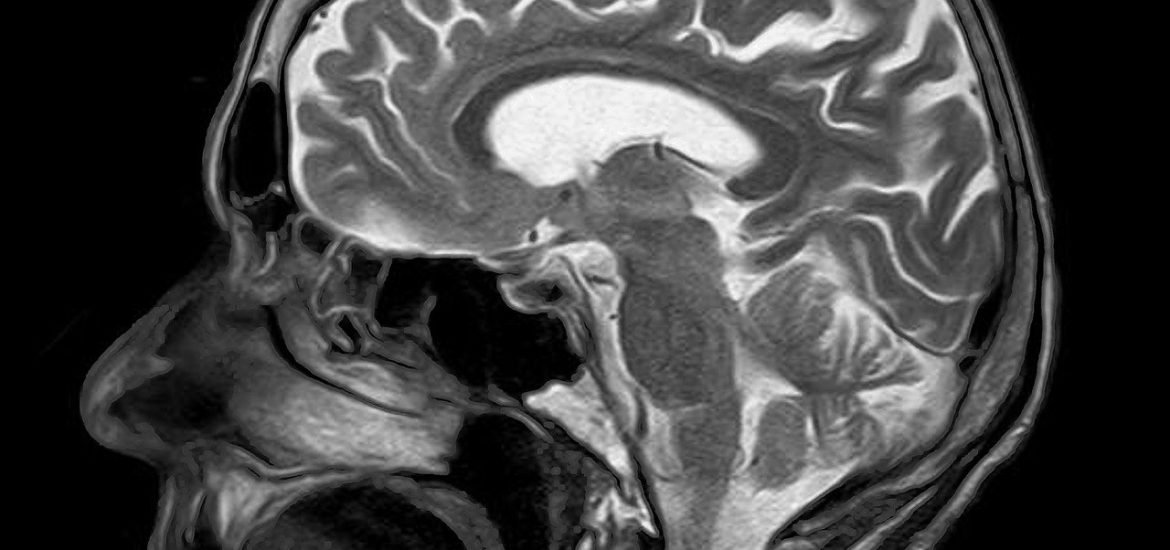

A team of researchers from King’s College London developed a new AI model to help radiologists identify brain abnormalities in MRI scans, including stroke, multiple sclerosis, and brain tumours, according to a study published in Radiology AI. The authors suggest that AI could address growing backlogs caused by shortages and the increasing demand for MRIs.

MRI scans are vital for diagnosing and monitoring a range of brain conditions such as tumours, strokes, and aneurysms. As a result, backlogs often lead to treatment delays and poorer patient outcomes. AI could be a valuable aid in easing pressure on radiology departments by triaging scans and increasing reporting speeds.